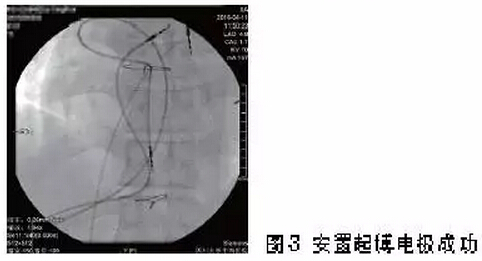

经心内科全科讨论,起搏介入组的方元教授和先心病介入组的冯沅教授制定了经肝静脉穿刺安置双腔起搏器的方案。患者在X线透视下,由消化科魏波医生穿刺肝静脉成功,经肝静脉置入两根8F可撕脱鞘。沿穿刺鞘置入心房和心室螺旋电极,固定稳妥,起搏阈值良好。于是术者在患者右上腹皮下做起搏器囊袋,置入起搏器脉冲发生器,并予以逐层缝合。术中及术后患者感觉良好。